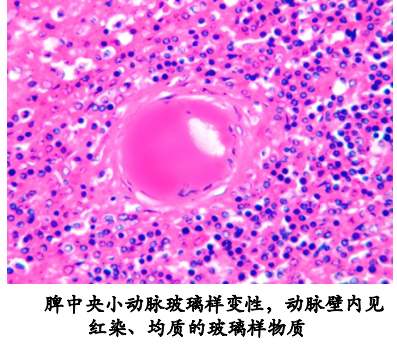

(3)细小动脉壁玻璃样变 |

高血压和糖尿病的肾、脑、脾等细小动脉。因血浆蛋白渗入和基底膜样物质沉积于血管壁,使动脉壁增厚、变硬, 管腔狭窄。动脉壁内见有均质、红染无结构的玻璃样物质。